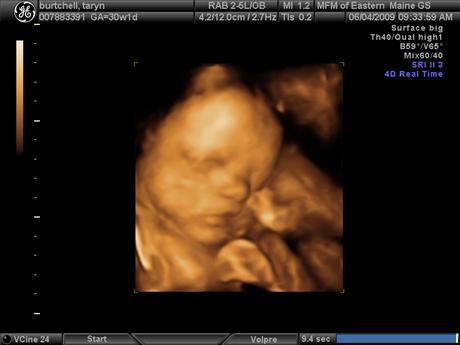

DH and i had our 3rd Level II 3D ultrasound and got to see baby Lauren again. She is doing great. Her left kidney has improved to normal developmental status and her right kidney is just under the cut-off to be considered normal, so it looks like her kidneys will be just fine. We go back in 6 weeks instead of 4 just to double check since it will be 3 weeks before she is due to arrive. She is 3.5 pounds exactly and is actually measuring a little on the big side, they said she is measuring in the 53rd percentile. She is still currently head down, basically in birthing position and has turned into a little gymnast with both feet by her head. The ultrasound tech said "it looked like she was picking her nose with her big toe" which you can see in one of the pictures. She has some shubby little cheeks!! And she has hair, DH and i weren't expecting that because we were both very bald babies so we are excited for some hair too!!

The first picture is the one with her big toe by her nose. I also added a new belly pic since i haven't taken one in a while. Image Attachment(s):